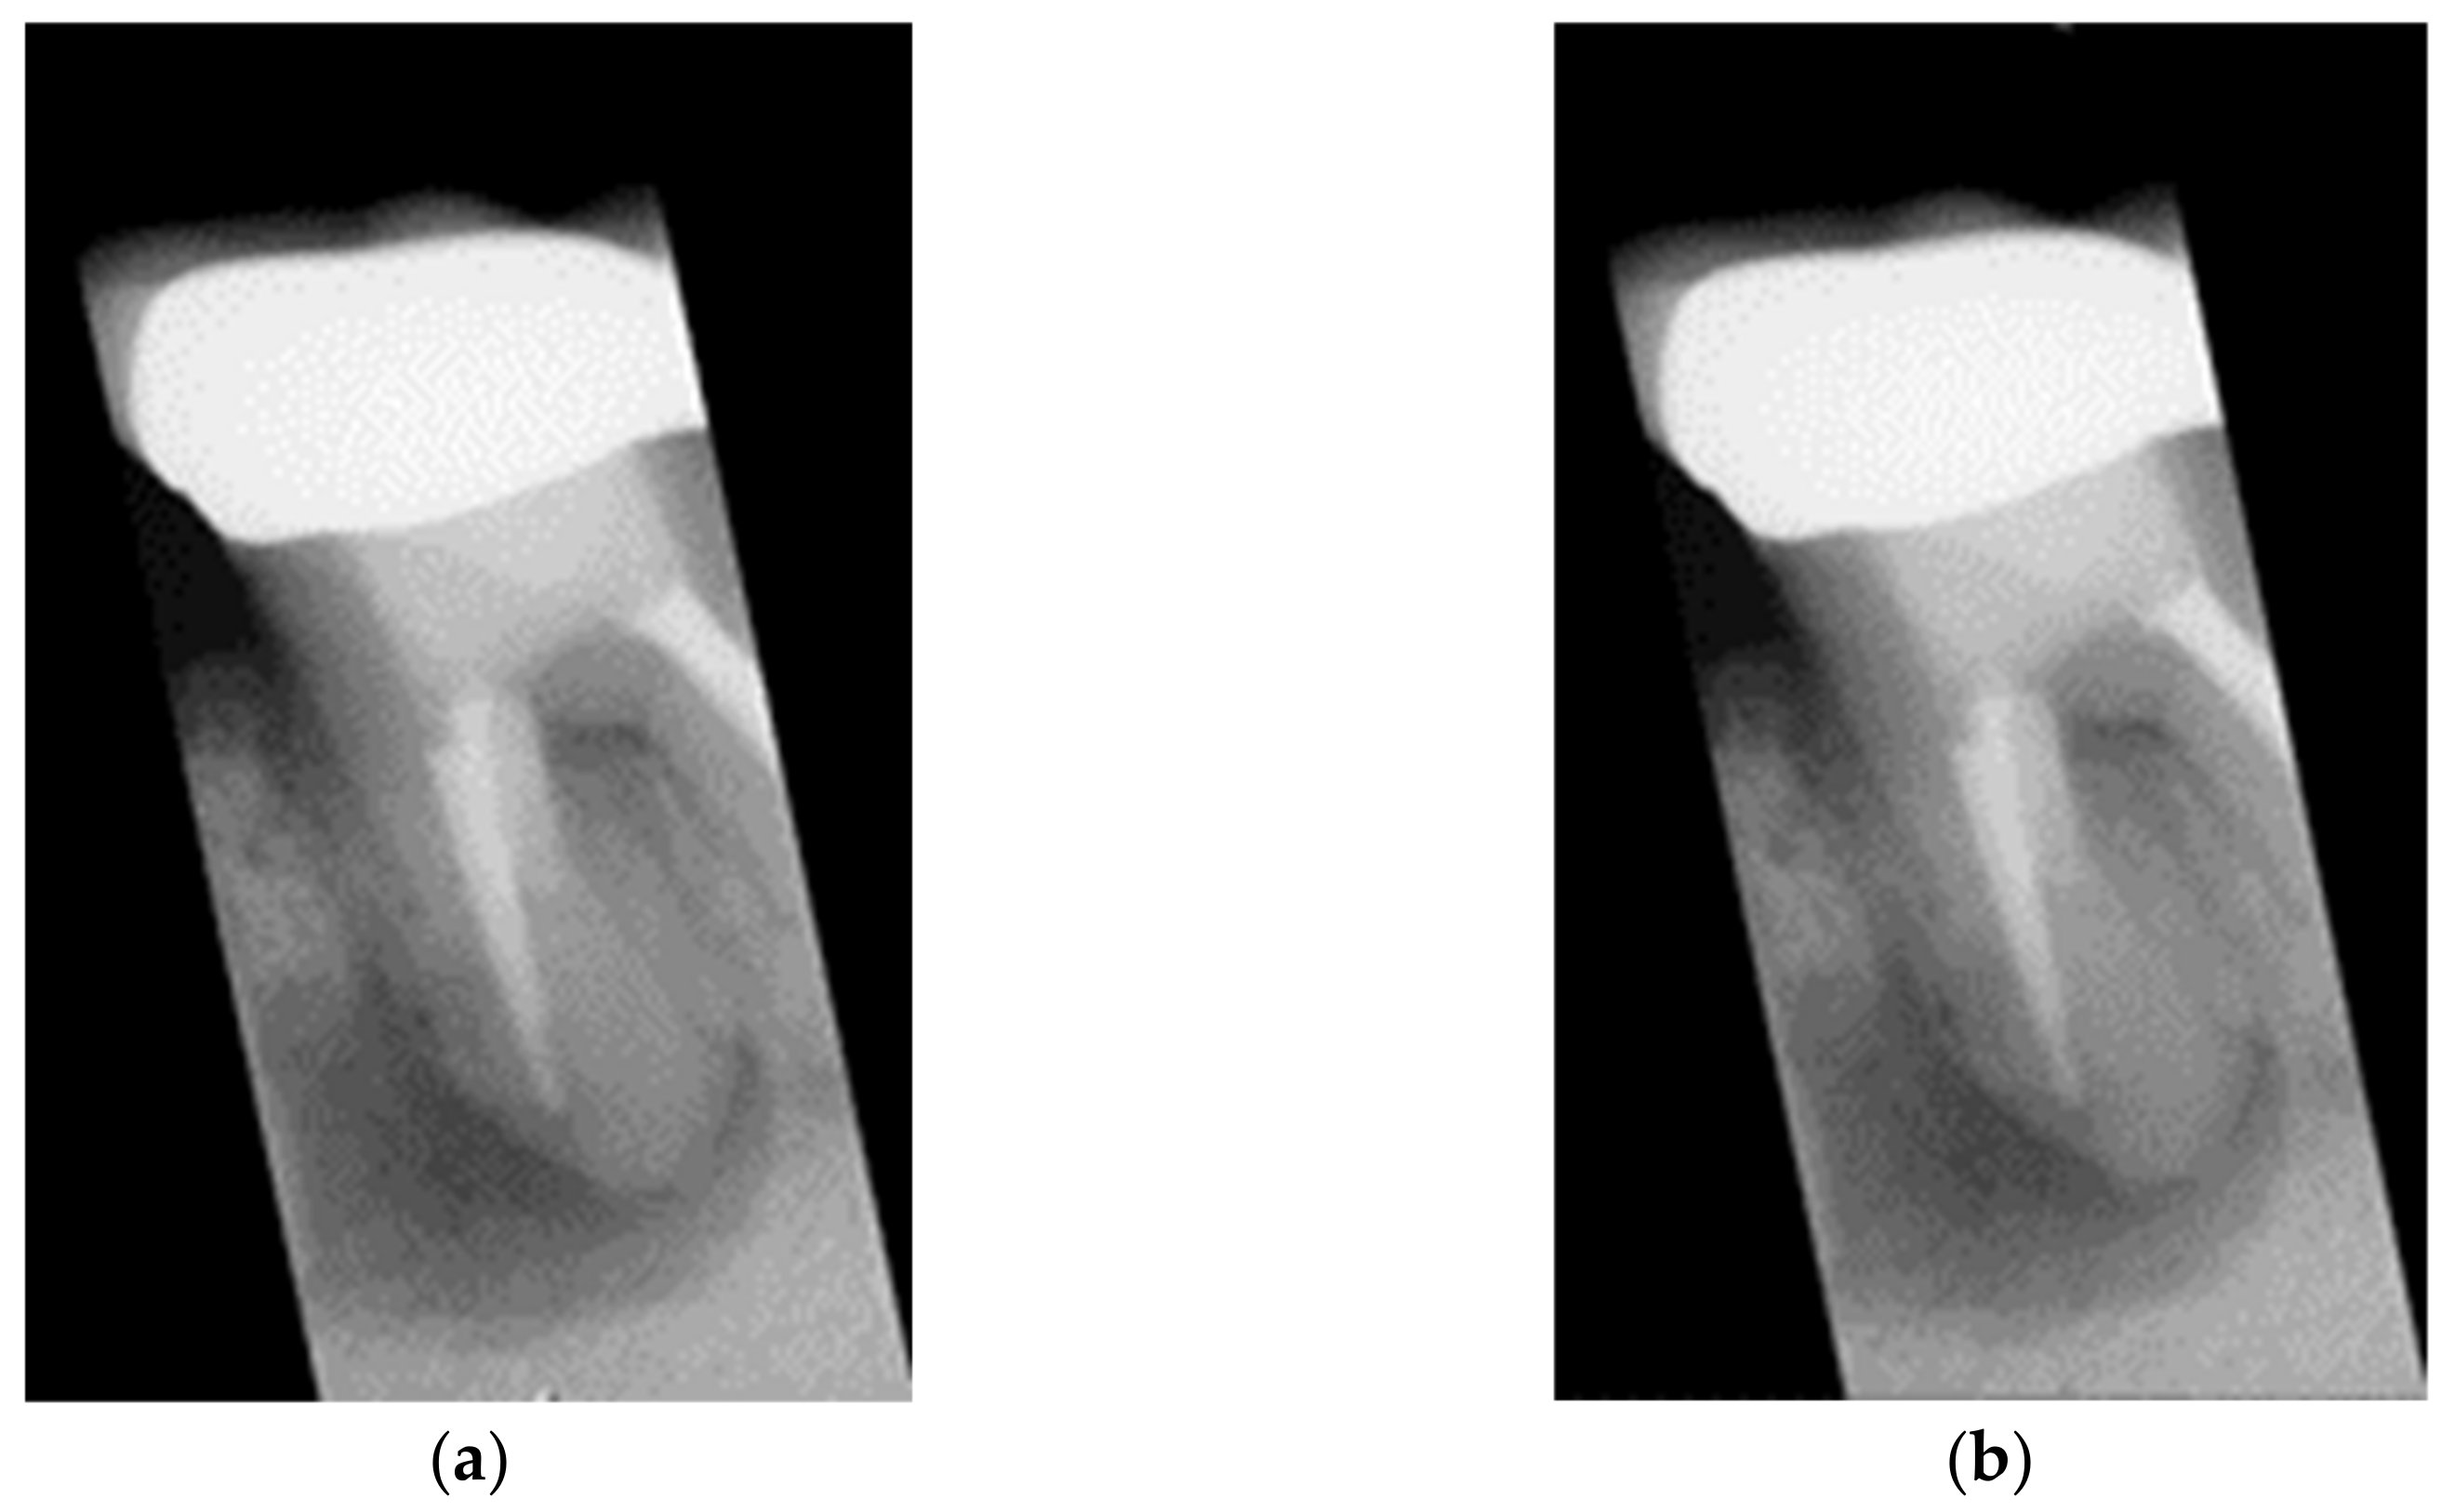

- In the image cropping preprocessing part, this study adds the adaptive threshold and angle rotation technology. Compared with the existing methods, this method significantly improves the image clarity and accuracy of a single tooth image.